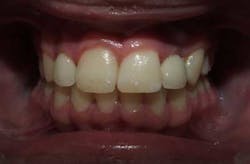

Corticotomy surgery was done and distal root movement was initiated on tooth No. 11 using a lever arm and elastic power chain. Root divergence was accomplished in eight weeks, and implant placement was accomplished at that time. The occlusion was detailed and orthodontic appliances were removed a short time later.

The patient reported mild to moderate pain from the corticotomy surgery that lasted for about a week. He was very satisfied with the treatment result and was happy with the decision to augment traditional treatment with periodontal surgery.

Periodontally accelerated osteogenic orthodontics is often used from the outset of orthodontic treatment in order to dramatically reduce treatment times for a comprehensive orthodontic case. In addition to this, it can be used in cases where specific tooth movement has become difficult in a localized area and additional help is needed. The patient discomfort from the procedure is normally tolerated well and healing is typically not difficult or prolonged. A combined periodontic-orthodontic approach can help treatment continue to progress in difficult cases.